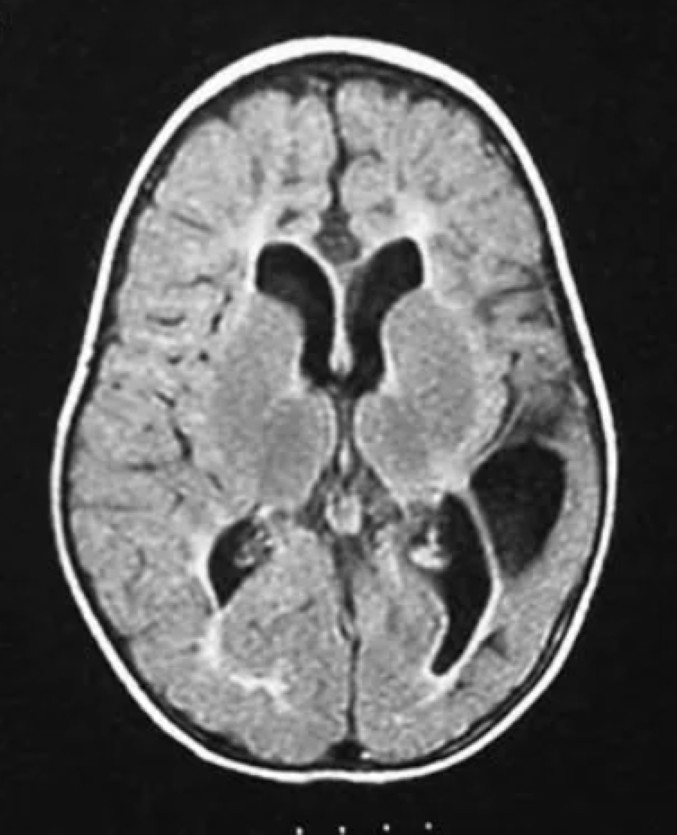

Cerebrale Parese is een aandoening veroorzaakt door beschadigingen in die delen van de hersenen die de mens in staat stelt spieren te gebruiken. “Cerebrale” betekent, dat de aandoening te maken heeft met de hersenen, en “parese” betekent zwakte van de spieren of het onvermogen van de spieren te werken.

Meestal ontstaat de beschadiging tijdens de zwangerschap, gedurende de bevalling, of kort na de geboorte. Er kan sprake zijn van een milde, matige of een ernstige aandoening. Bij een milde Cerebrale Parese is de motoriek van het kind wat onhandig. Matige Cerebrale Parese wil zeggen dat het kind moeilijk loopt of een hulpmiddel nodig heeft. Een kind met ernstige CP heeft een rolstoel nodig. De hersenaandoening wordt niet groter naarmate het kind ouder wordt, maar de gevolgen, zwakte en onvermogen van de spieren, kunnen wel verergeren.